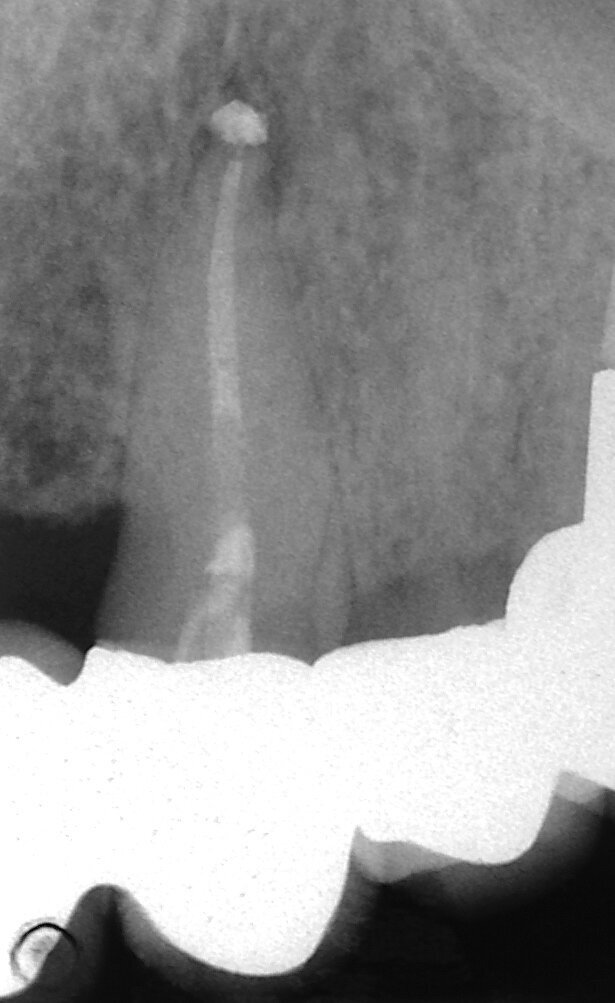

Vital pulp therapy has become more popular in recent years. Calcium hydroxide has been the most common material for pulp capping, but MTA has shown even better results in biocompatibility and outcome.[3] Cases with large carious pulp exposure can be treated successfully with partial pulpotomy and MTA as a capping agent, keeping teeth vital (Figs. 1a–e).

Fig. 1a: (a) Deep carious lesion. (b) Partial pulpotomy. (c) MTA application with the MAP System and PD MTA White. (d) Filling. (e) Post-op radiograph showing the pulp capping with MTA.

Fig. 1b: (a) Deep carious lesion. (b) Partial pulpotomy. (c) MTA application with the MAP System and PD MTA White. (d) Filling. (e) Post-op radiograph showing the pulp capping with MTA.

Fig. 1c: (a) Deep carious lesion. (b) Partial pulpotomy. (c) MTA application with the MAP System and PD MTA White. (d) Filling. (e) Post-op radiograph showing the pulp capping with MTA.

Fig. 1d: (a) Deep carious lesion. (b) Partial pulpotomy. (c) MTA application with the MAP System and PD MTA White. (d) Filling. (e) Post-op radiograph showing the pulp capping with MTA.

Fig. 1e: (a) Deep carious lesion. (b) Partial pulpotomy. (c) MTA application with the MAP System and PD MTA White. (d) Filling. (e) Post-op radiograph showing the pulp capping with MTA.